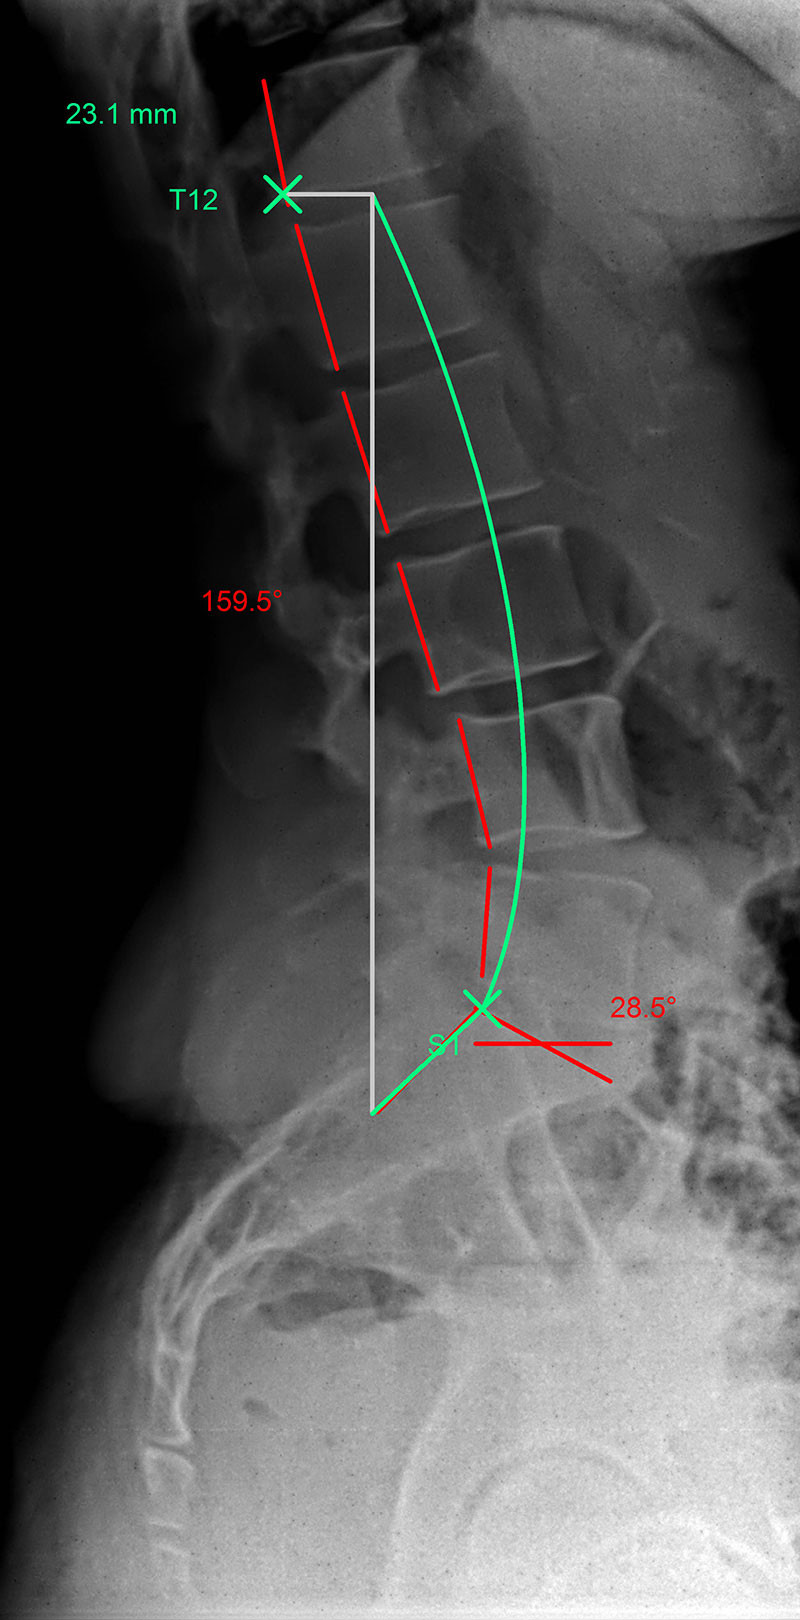

Hypolordosis: |

The green line represents the ideal spinal curvature and the red line that of the patient’s spine in profile view.